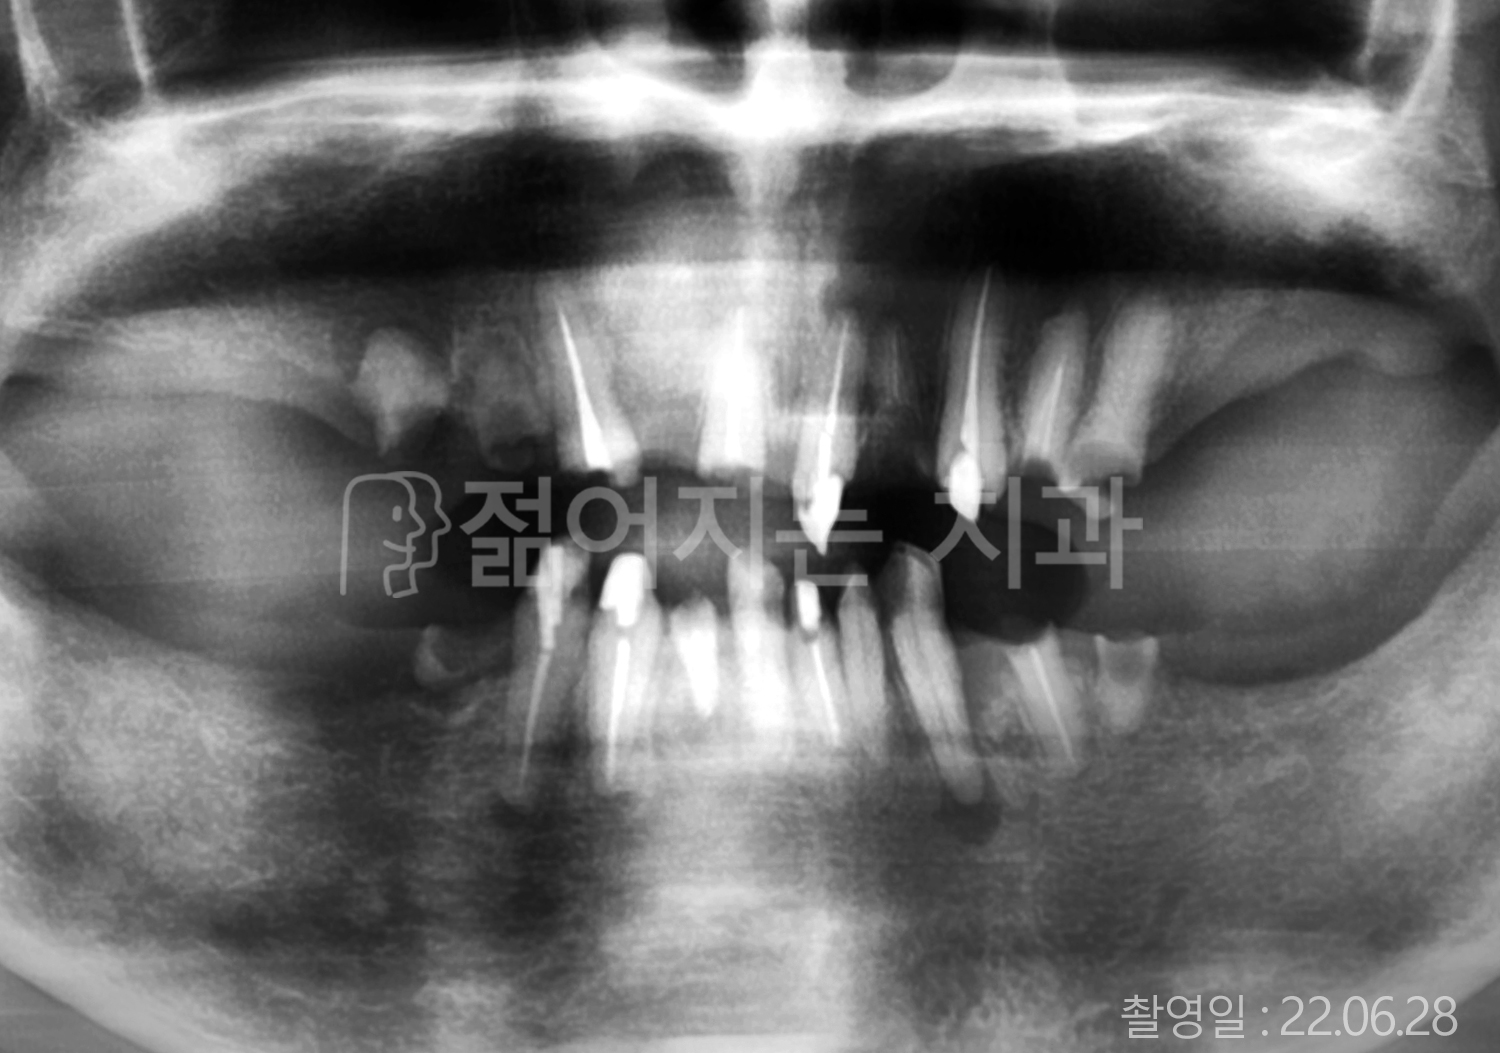

• 70대 고혈압, 당뇨 전체치아 10개 이상 임플란트

• 50대 고혈압, 당뇨 전체치아 10개 이상 임플란트

• 60대 고혈압, 당뇨 전체치아 10개 이상 임플란트

• 50대 전체치아 10개 이상 임플란트

• 70대 당뇨 전체치아 10개 이상 임플란트

• 80대 전체치아 10개 이상 임플란트

• 40대 전체치아 10개 이상 임플란트

• 60대 고협압, 고지혈증 전체치아 10개 이상 임플란트

• 60대 전체치아 10개 이상 임플란트